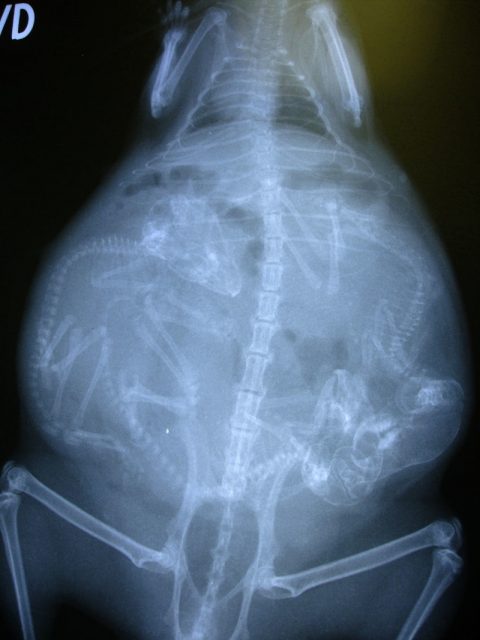

Хээл авсан амьтадын хэвлийн рентген зураг ингэж харагддаг. Хэдий итгэмээргүй ч ийм л байна.